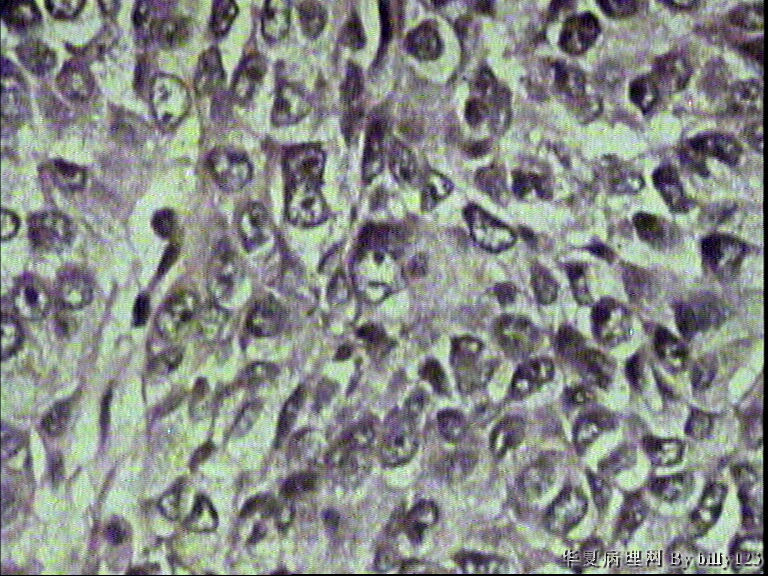

支气管活检,患者,男性,66岁,支气管镜下见息肉样新生物,鳞癌吗?请各位老师指教!

图1

图2

图3

图4

图5

图6

图7

图8